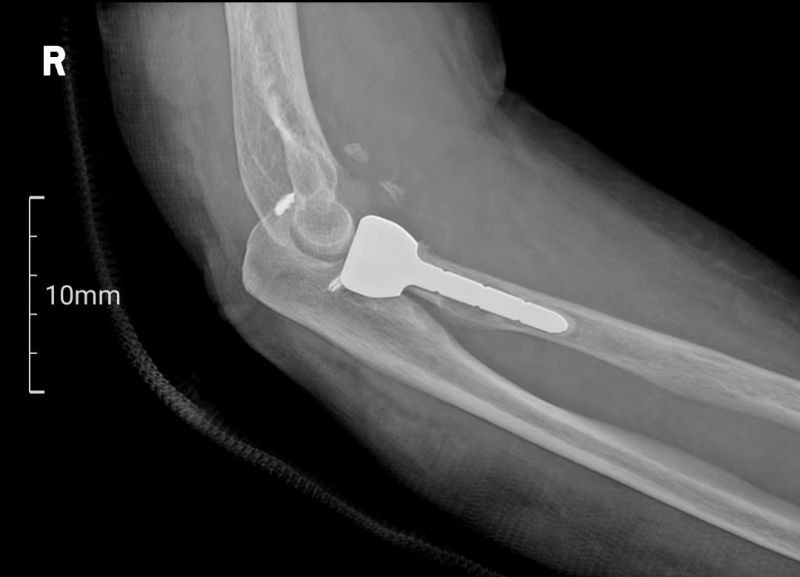

患者梁女士因不慎跌倒导致右肘关节疼痛并活动受限,经X线检查确诊为肘关节恐怖三联征。面对这一复杂病情,张立主任迅速组织科室医生及3D打印中心技术人员进行病例讨论,并决定采用3D打印桡骨小头置换术进行治疗。

术前,南溪山医院3D打印中心利用高精度扫描技术获取患者肘关节的三维数据,并进行参数化分析,为患者量身定制了3D打印桡骨小头假体。这一假体不仅与患者骨骼高度匹配,还能在手术中即插即用,极大地缩短了手术时间,并确保了手术的精准性和安全性。

手术由张立主任及贵鹏医师团队共同完成。术中,医生们通过5厘米的切口暴露骨折部位,并依据术前规划精准处理骨折断端。随后,3D打印桡骨小头假体被顺利植入,实现了对桡骨头关节面的完美重建。术后,患者恢复顺利,基本功能得到有效恢复。